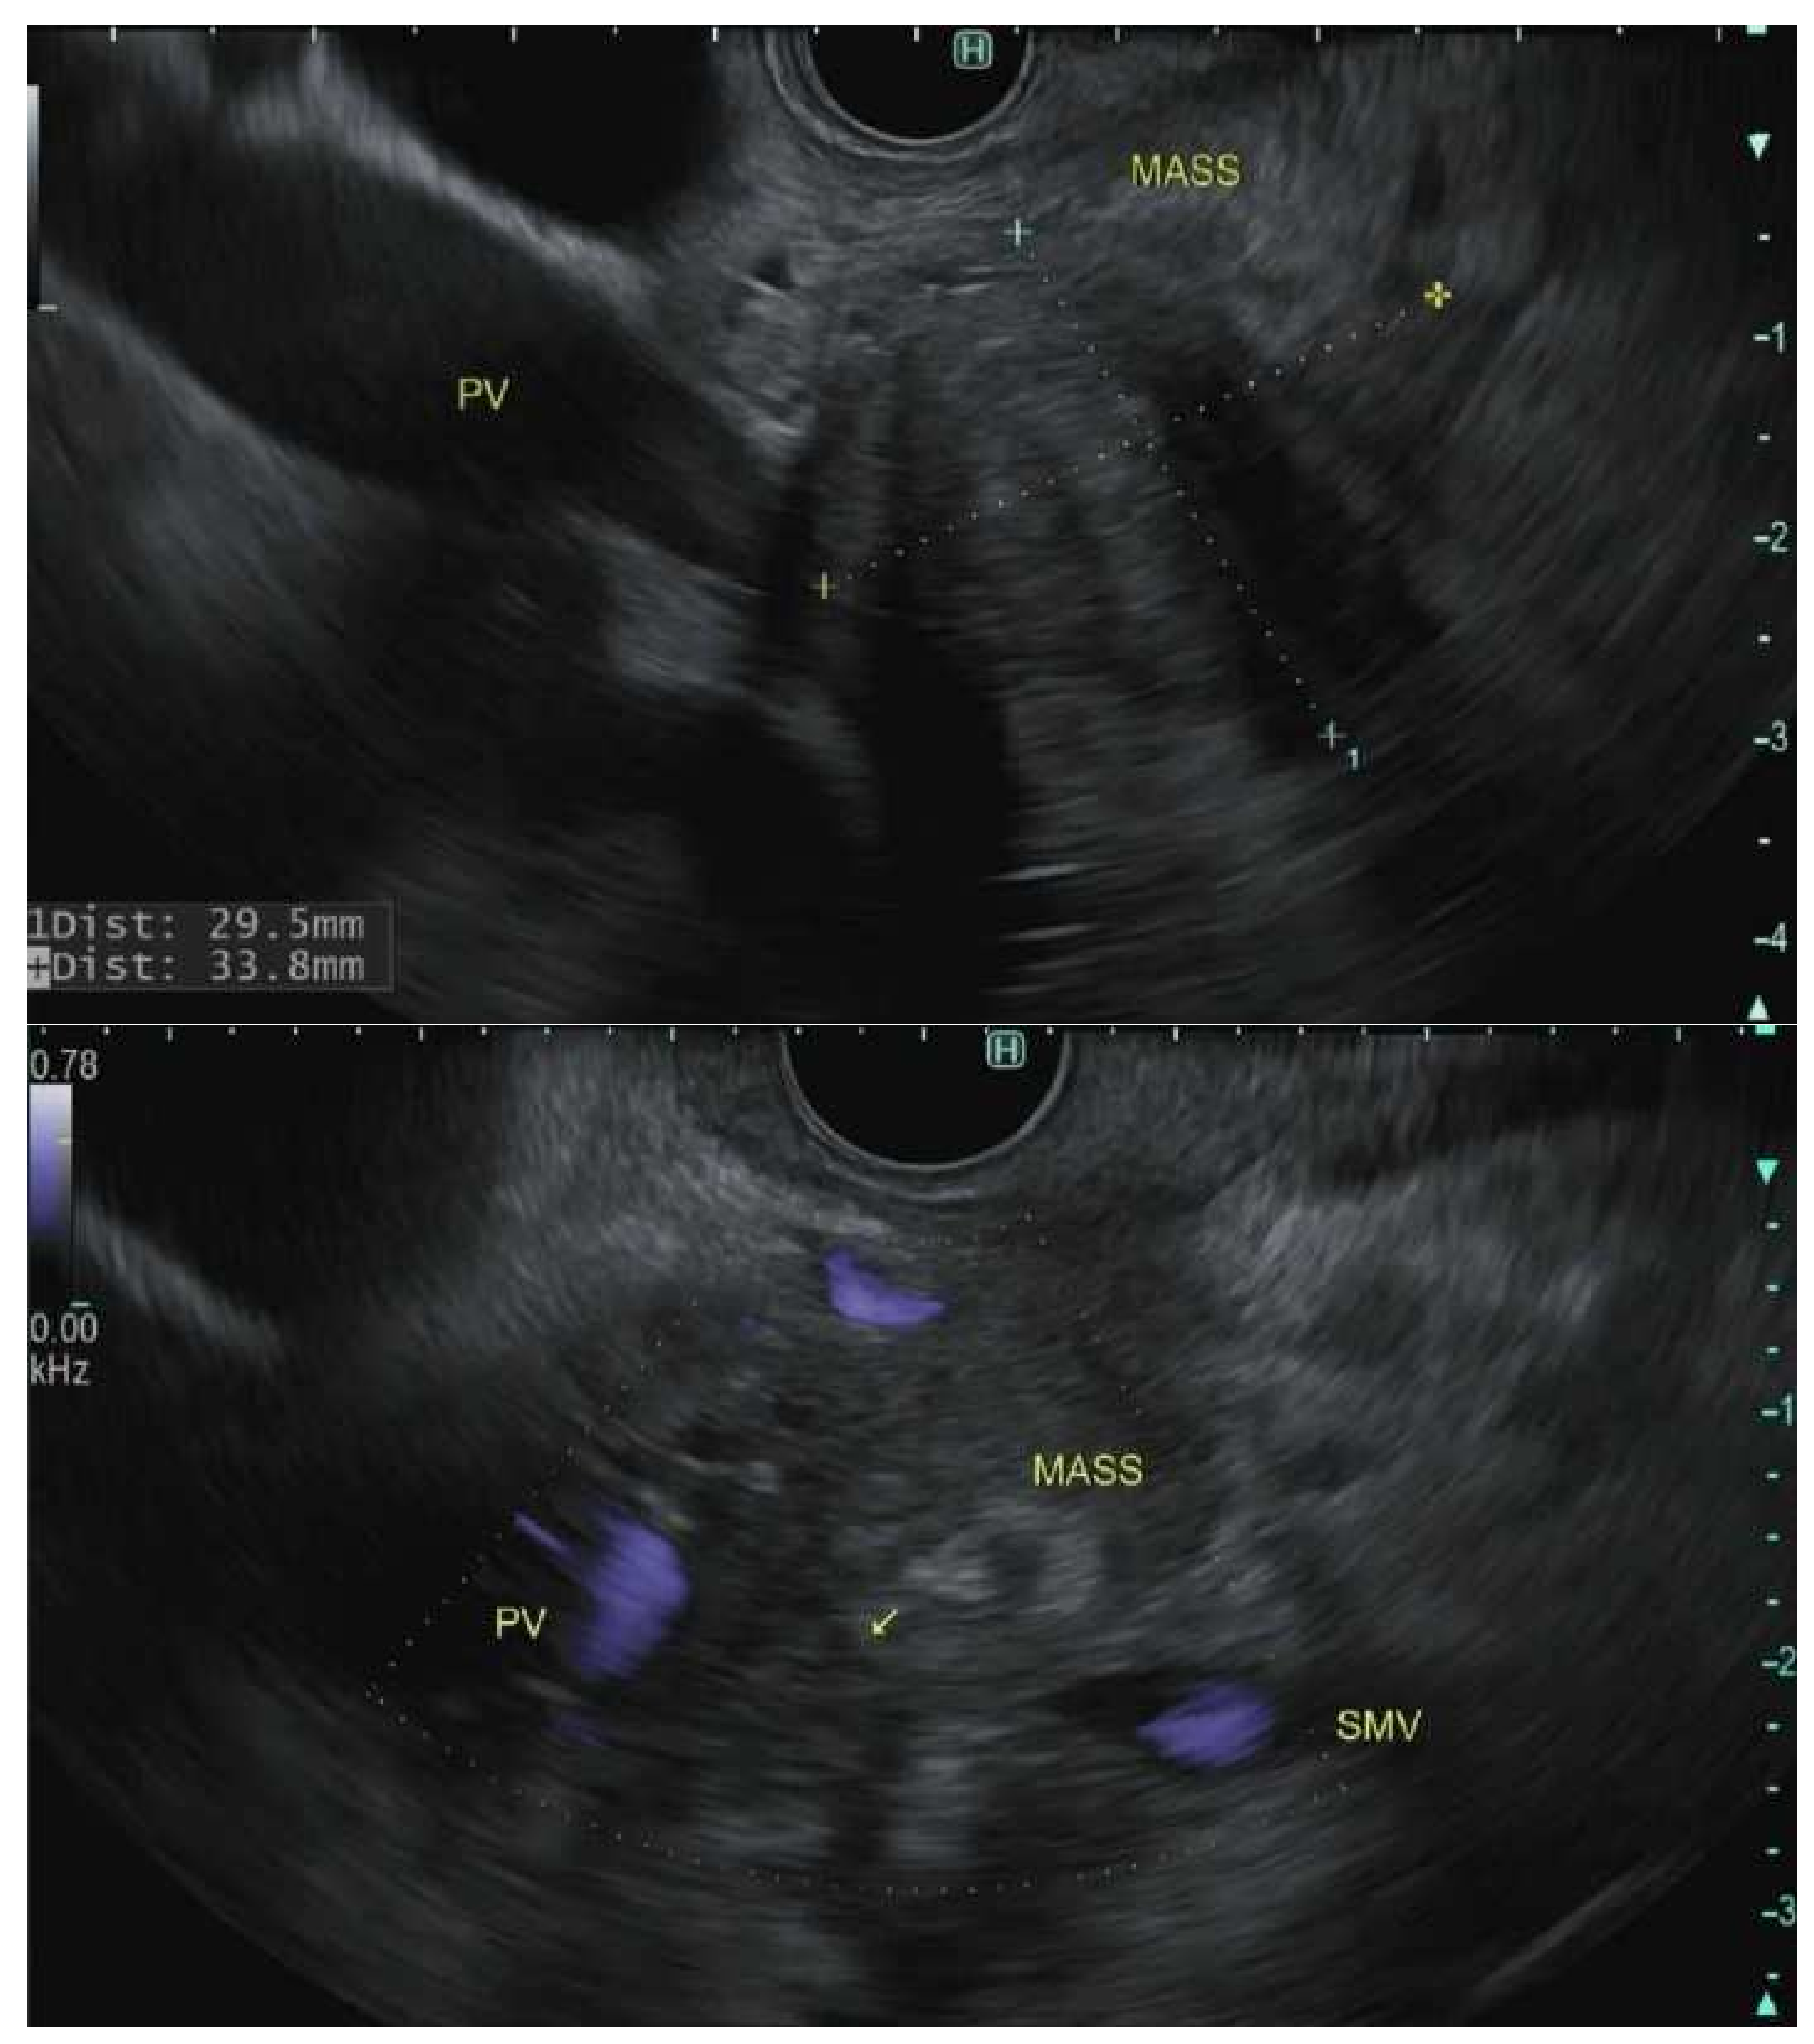

7. Staging

- Yang, R.; Lu, M.; Qian, X.; Chen, J.; Li, L.; Wang, J.; Zhang, Y. Diagnostic accuracy of EUS and CT of vascular invasion in pancreatic cancer: A systematic review. J. Cancer Res. Clin. Oncol. 2014, 140, 2077–2086. [Google Scholar] [CrossRef] [PubMed]

- Nawaz, H.; Fan, C.Y.; Kloke, J.; Khalid, A.; McGrath, K.; Landsittel, D.; Papachristou, G.I. Performance characteristics of endoscopic ultrasound in the staging of pancreatic cancer: A meta-analysis. JOP J. Pancreas 2013, 14, 484–497. [Google Scholar] [CrossRef]

- Sugiyama, M.; Hagi, H.; Atomi, Y.; Saito, M. Diagnosis of portal venous invasion by pancreatobiliary carcinoma: Value of endoscopic ultrasonography. Gastrointest. Radiol. 1997, 22, 434–438. [Google Scholar] [CrossRef]

- Rösch, T.; Dittler, H.-J.; Strobel, K.; Meining, A.; Schusdziarra, V.; Lorenz, R.; Allescher, H.-D.; Kassem, A.M.; Gerhardt, P.; Siewert, J.-R.; et al. Endoscopic ultrasound criteria for vascular invasion in the staging of cancer of the head of the pancreas: A blind reevaluation of videotapes. Gastrointest. Endosc. 2000, 52, 469–477. [Google Scholar] [CrossRef]

- Glazer, E.S.; Rashid, O.M.; Klapman, J.B.; Harris, C.L.; Hodul, P.J.; Pimiento, J.M.; Malafa, M.P. Endoscopic ultrasonography complements computed tomography in predicting portal or superior mesenteric vein resection in patients with borderline resectable pancreatic carcinoma. Pancreatol. Off. J. Int. Assoc. Pancreatol. (IAP) 2017, 17, 130–134. [Google Scholar] [CrossRef]